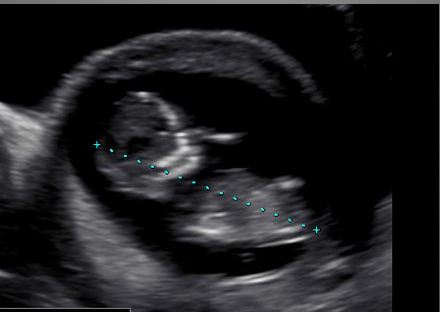

I hope you may be able to see a nub and be able to give me an idea of whether we have a pinkie or a bluey coming!! These pics were from about 12+5.